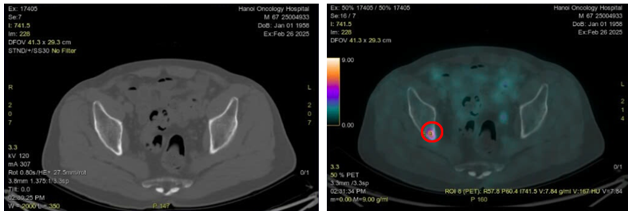

Hình 6: Hình ảnh CT cấu trúc bình thường (bên trái) và hình ảnh tăng hoạt tính phóng xạ ở xương ức trên PET/CT (vòng tròn màu đỏ) (SUVmax: 18,1)

Hình 7: Hình ảnh CT cấu trúc bình thường (bên trái) và hình ảnh tăng hoạt tính phóng xạ ở xương chậu phải trên PET/CT (vòng tròn màu đỏ) (SUVmax:7,84)

-         Sau khi chụp PET/CT để đánh giá giai đoạn trước điều trị phát hiện tổn thương thứ phát tại xương ức và xương chậu phải, dù trên hình ảnh CT không phát hiện sự biến đổi về mặt cấu trúc tương ứng với vị trí các xương này. Về mặt lý thuyết sự biến đổi về mặt chức năng thường xảy ra trước khi có sự biến đổi về mặt cấu trúc với thời gian khoảng 6 tháng.

-         Việc ghi hình PET/CT giúp phát hiện và định vị chính xác vị trí tổn thương di căn từ đó giúp xác định chính xác giai đoạn bệnh. Đối với trường hợp bệnh nhân trên nếu chỉ dựa trên kết quả chụp chiếu CT đơn thuần sẽ bỏ sót các tổn thương thứ phát ở xương. Việc chụp PET/CT giúp phát hiện các tổn thương di căn tại vị trí xương ức và xương chậu dẫn tới sự thay đổi về hướng điều trị, cu thể trên bệnh nhân này không còn chỉ định phẫu thuật hay xạ trị triệt căn nữa và sẽ tiến hành điều trị toàn thân và chăm sóc giảm nhẹ.